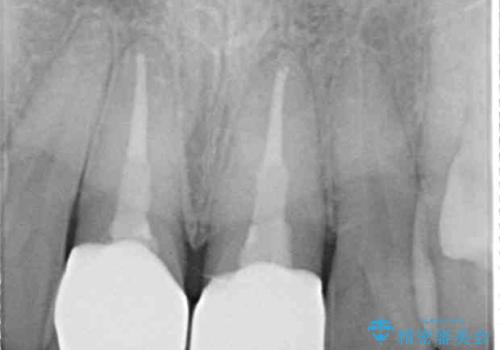

- 神経を取り除いたことで経年変色した前歯2本を気にして来院された患者様です。

根管治療を行う必要はないと判断し、双方の歯にグラスファイバーを含有した土台を植立してオールセラミッククラウンにて補綴することとしました。

色調が周囲の歯とアウトともに、表面のつぎはぎや穴を封鎖した際の段差などが解消され、天然歯のような感触となりました。